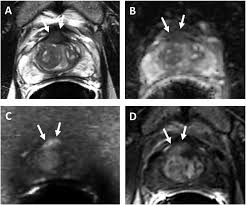

Revisiting Quantitative Multi Parametric Mri Of Benign Prostatic Hyperplasia And Its Differentiation From Transition Zone Cancer Springerlink

Revisiting Quantitative Multi Parametric Mri Of Benign Prostatic Hyperplasia And Its Differentiation From Transition Zone Cancer Springerlink from media.springernature.com